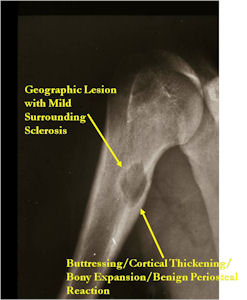

Plain X-rays:

- Geographic, circumscribed lesion usually around 5cm in size.

- There may be expansion of bone, cortical thinning and cortical breakthrough. A soft tissue mass may accompany this lesion but the soft tissue component is usually contained by the periosteum.

- The periosteum remains intact around the soft tissue component. Might need a CT scan to detect the subtle calcification (Egg Shell Rim of Calcification) associated with an intact periosteal reaction

- The lesion may be entirely radiolucent but usually shows some degree of mineralization. Mineralization may appear stippled like cartilage but do not see chondroid pathologically. Mineralization is sometimes better detected on a CT scan rather than an x-ray.

- Usually less surrounding sclerosis than an osteoid osteoma.

- Arise from the Diaphysis (75%) more commonly than Metaphyseal (25%)

- 4 cm to 6 cm in size